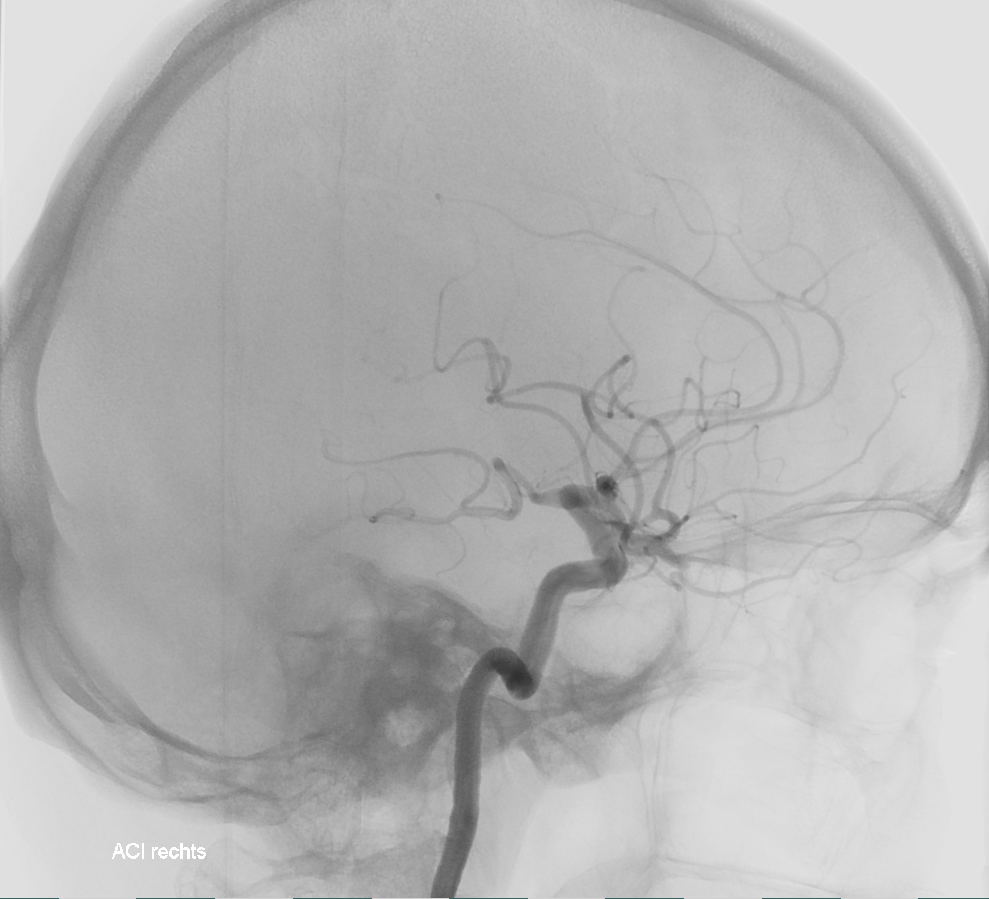

ICA Angiographie AP

Darstellung der Arteria carotis interna in einer Angiographie im AP Strahlengang.